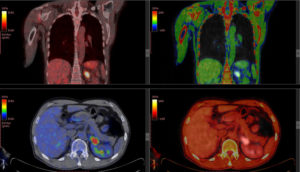

Positron emission tomography, or PET scan, is a kind of imaging that uses small particles entered into the bloodstream in order to view bodily organs by using the flow of blood as a delivery mechanism. Before a PET scan, a radiologist will inject a liquid containing small amounts of radiation into your vein, allowing it to spread through the bloodstream. Blood usually collects near affected organs, meaning this liquid will do the same. A scanner can then be passed over your body to pick up radiation in the blood, and the images are transmitted to a computer for viewing.

A PET scan is most often used for organ and blood-related disorders, as well as documenting certain brain activity. They can also be used to test various forms of treatment for cancer and other illnesses. One of the main differences between MRI and PET scans is that a PET scan produces less detailed images. Because of this, you may see your radiologist use a PET-CT scan, which combines the images of both tools to create a more accurate picture. This is especially common when scans are being used to identify cancers.

- Cancer Detection and Monitoring: PET scans are highly effective in identifying cancerous cells and monitoring the effectiveness of cancer treatment.

- Combination Scans: Can be combined with CT scans (PET-CT) to provide more detailed information.

- PET Scan: PET scans are excellent for showing how well different parts of the body are working, and they are known as functional imaging. They provide information about the metabolic activity of tissues, which is crucial for detecting cancers, assessing brain function, and monitoring the effects of various treatments. In certain situations, PET scans can identify abnormalities even before structural changes show up on CT or MRI.